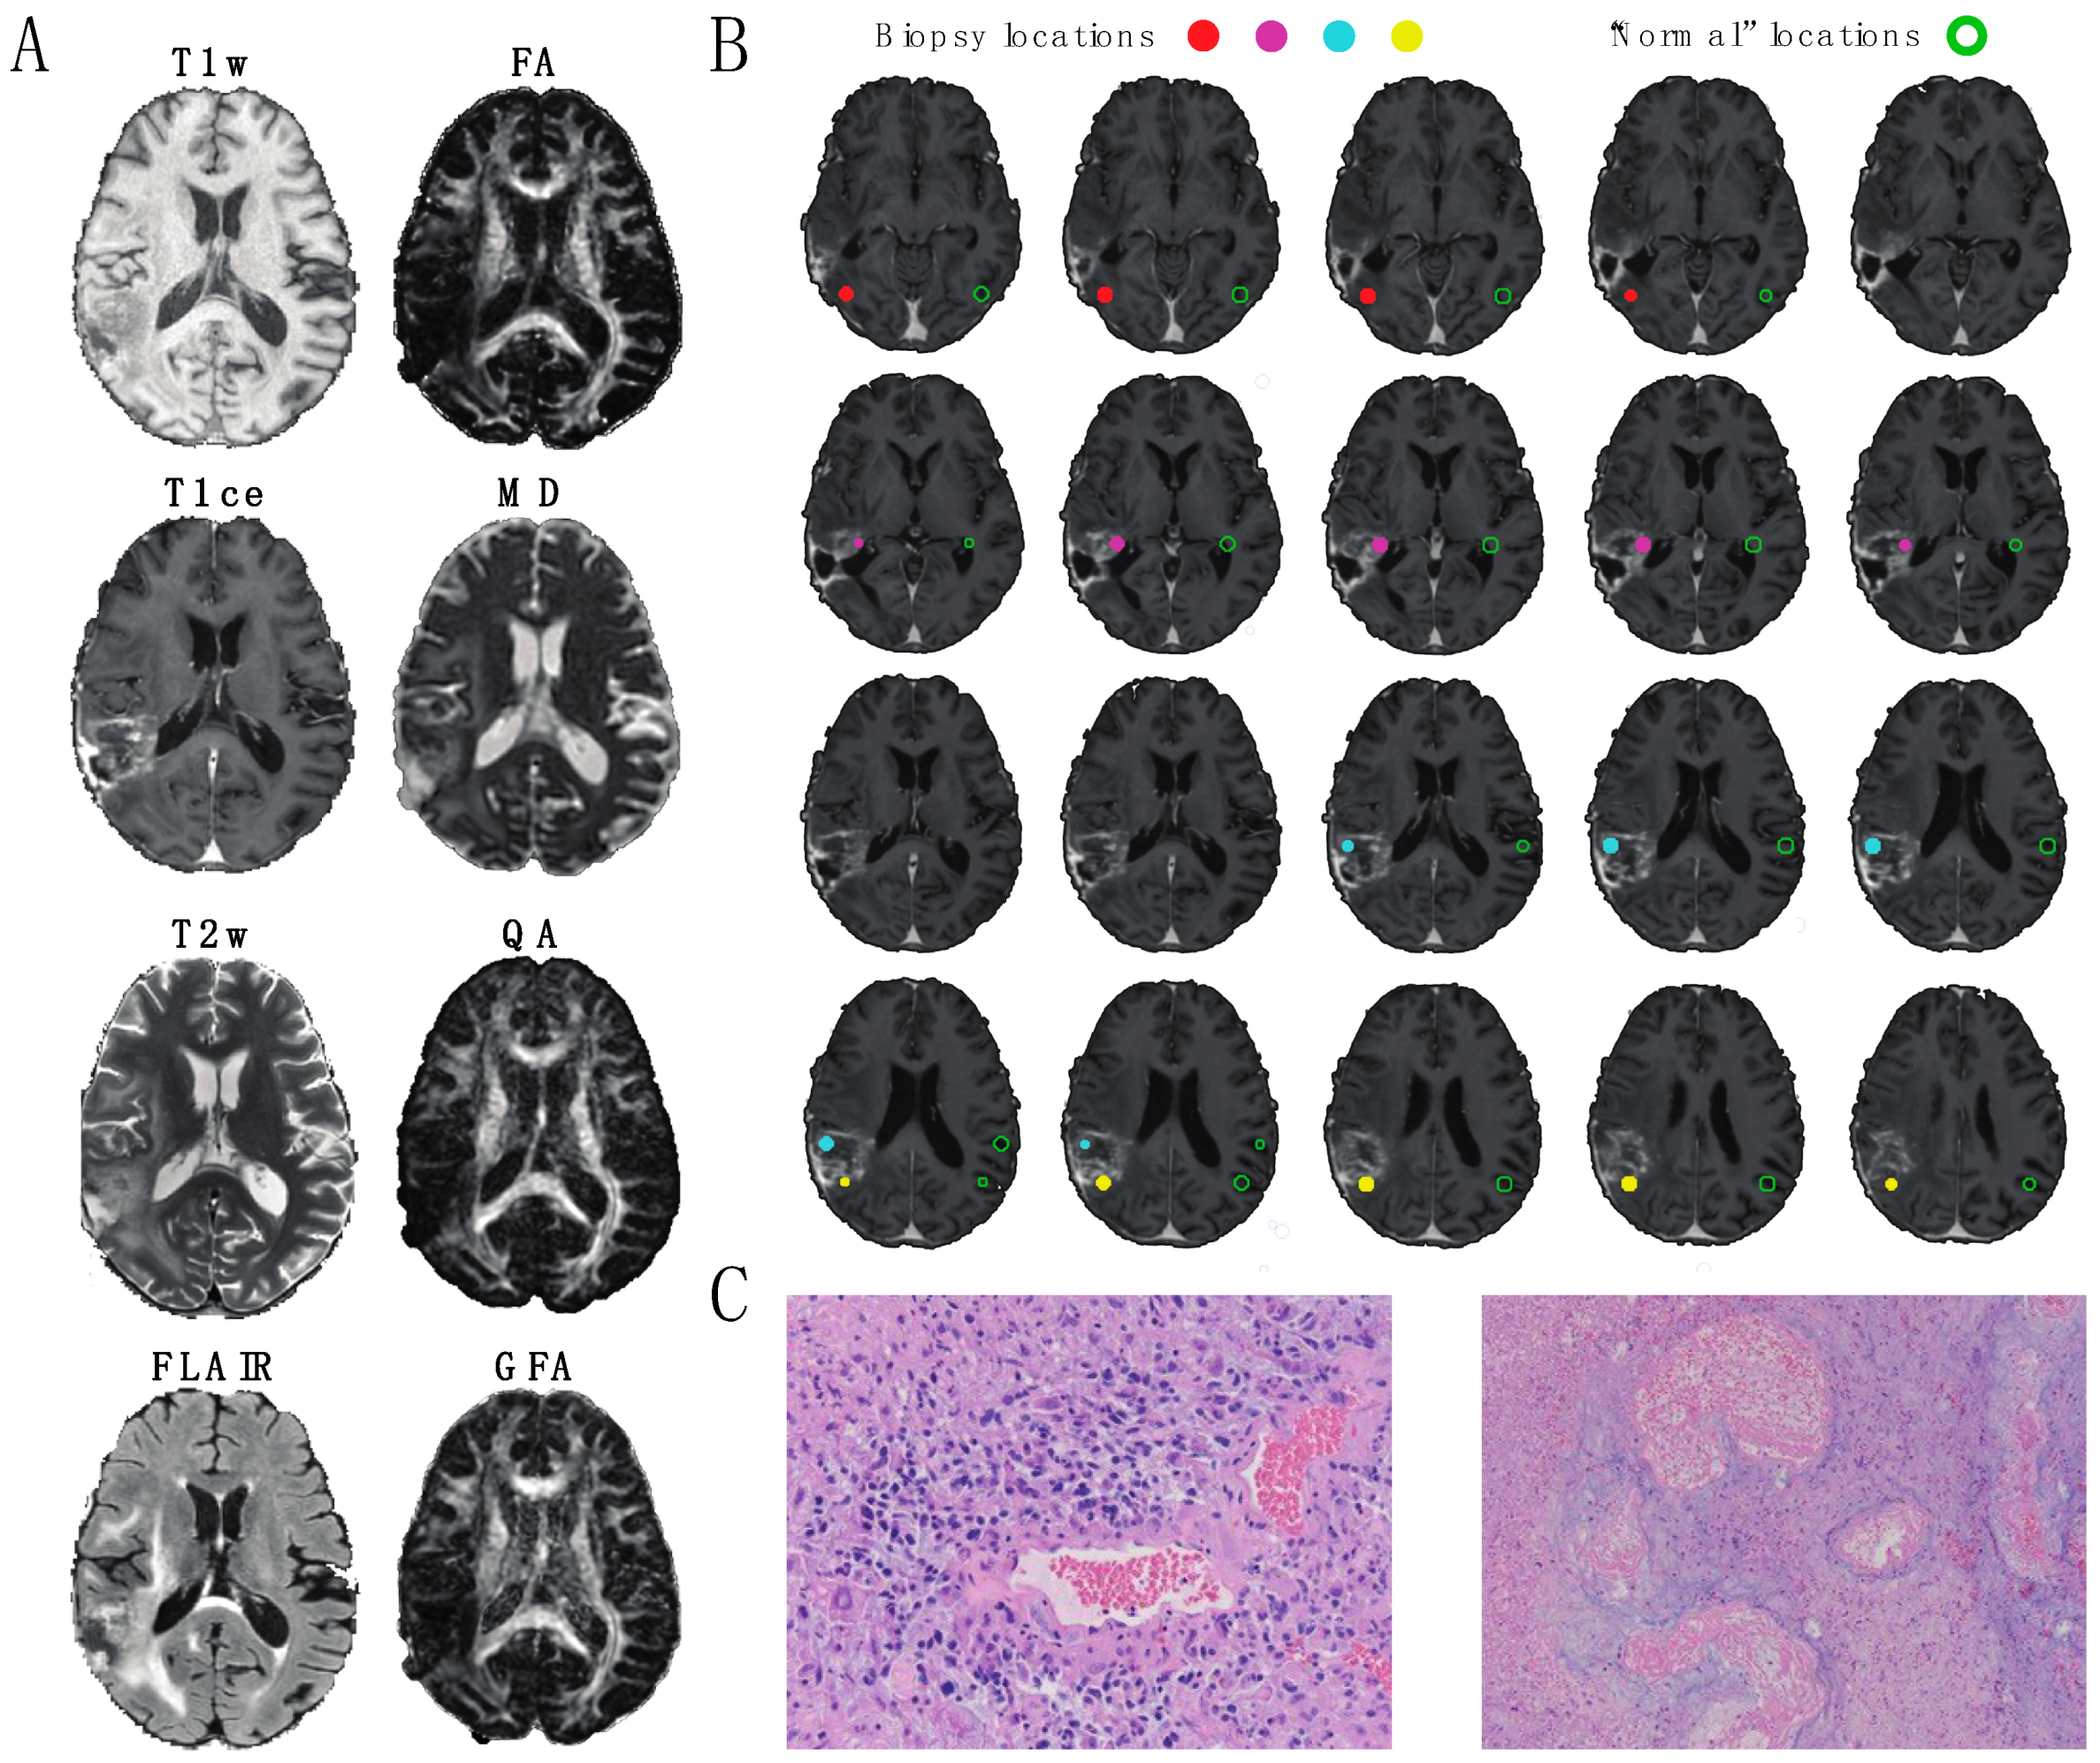

3.1. Image Analysis of Biopsy Classifications